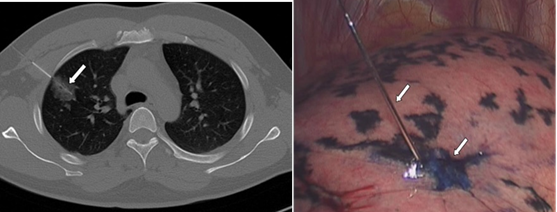

TOP10、CT穿刺对于肺结节的应用有哪些?

张伟:一、需要手术切除的磨玻璃结节,术前精准定位。CT引导下将钢丝钩放置在病灶周围, 并注入亚甲蓝染色,便于外科医生手术的切除(如图)。二、实性结节的穿刺活检。1.良恶性难于判定的实性结节,穿刺明确病理;2.晚期没有手术机会的肿瘤患者,穿刺明确病理及基因检测结果。三、对于磨玻璃结节的活检一般不做推荐,因为磨玻璃病灶不够密实,穿刺很难取得想要的阳性结果,而且还容易产生咯血等并发症。